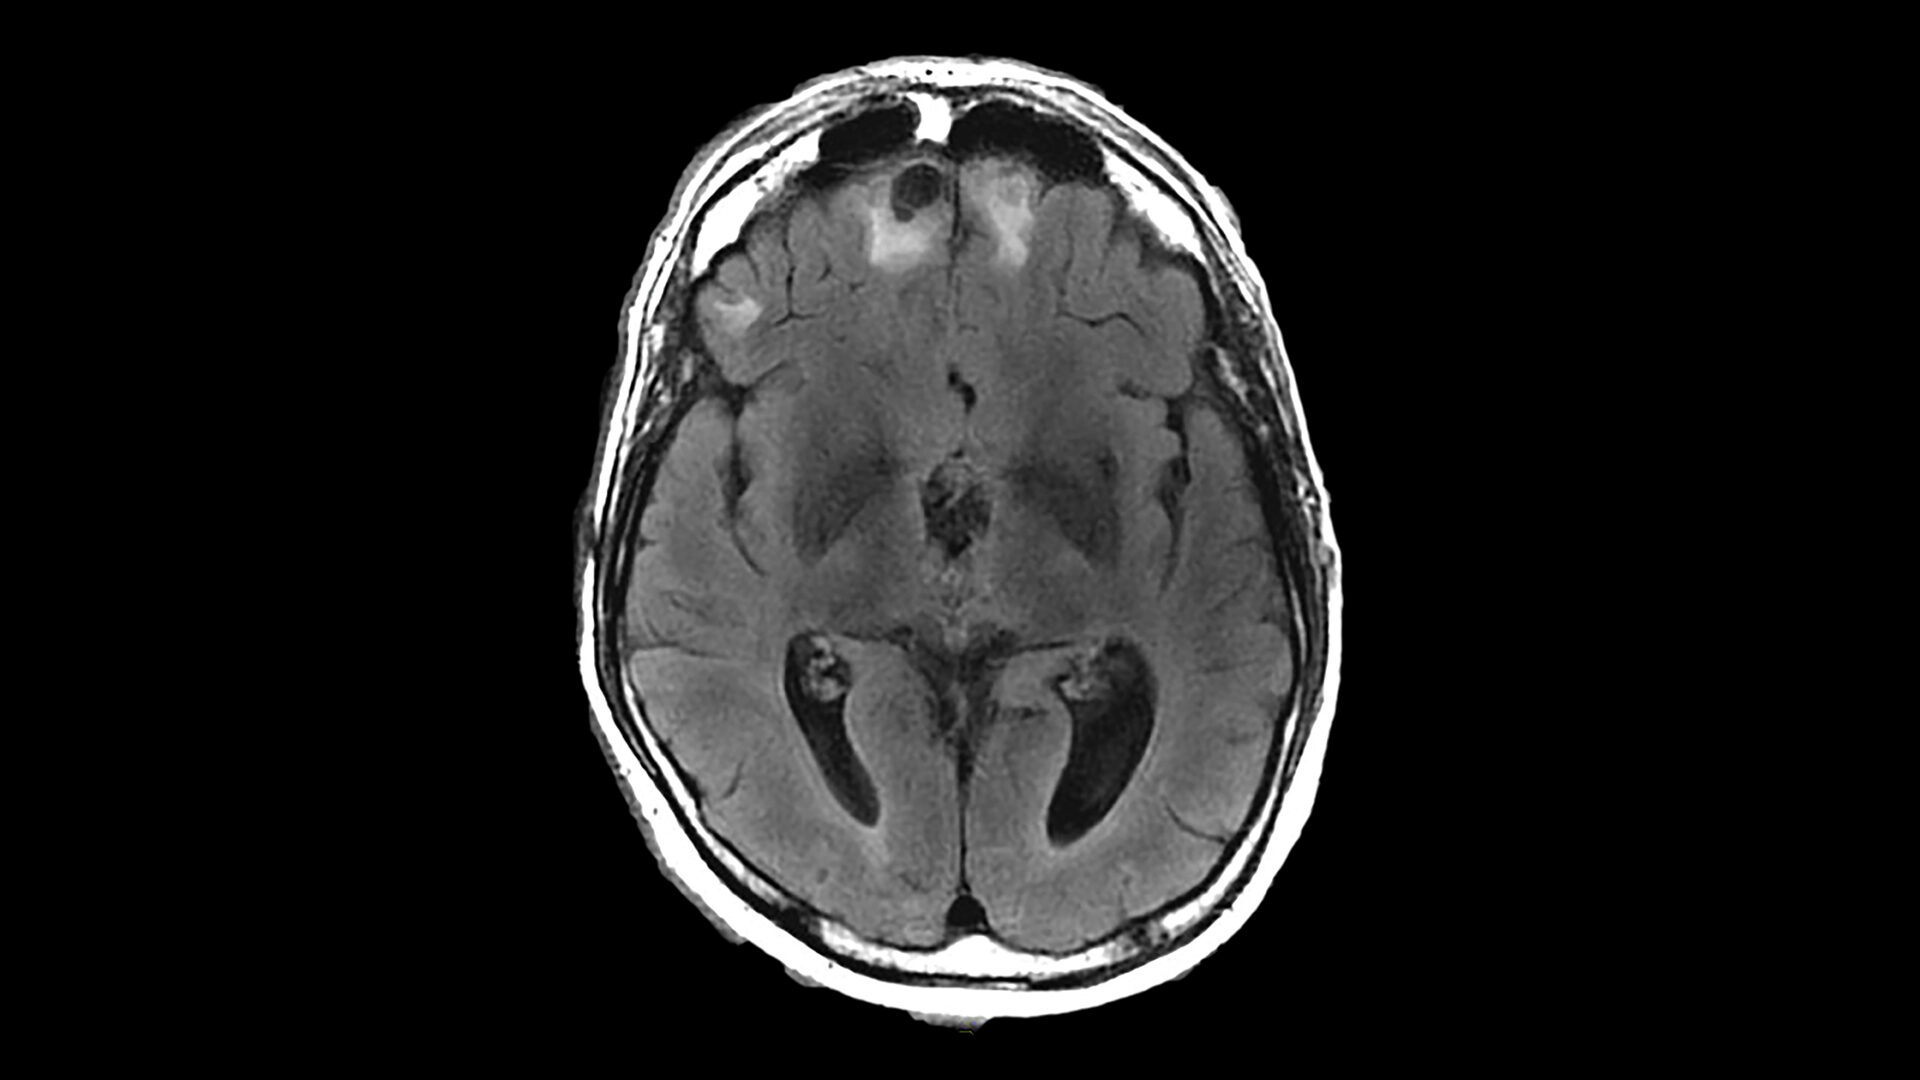

In autopsy analyses, CTE is often marked by shrinking of the brain and the presence of tau protein deposits in sulci near blood vessels.

Researchers found that the football players had shallower left superior frontal sulci on average than their non-football counterparts. Left superior frontal sulci are located on a main groove that runs along the top, front, left side of the brain, which is known to be physiologically affected in CTE.

The study also showed that football players with increasing years of playing experience had wider left occipitotemporal sulci than men who started later or had shorter careers. It is unclear why differences were detected only on one side of the brain and not in the sulci on both hemispheres, the researchers say.

Regarding a potential pathological mechanism, the authors note that models of brain biomechanics suggest that mechanical strain to the brain concentrates, in part, at the depths of sulci. This localized strain may disrupt axonal integrity and trigger the initiation of tau pathology, which, over time, can drive neuroinflammation, neuronal loss, and cortical atrophy, potentially leading to structural changes of sulcal widening and shallowing, as reported in the study.